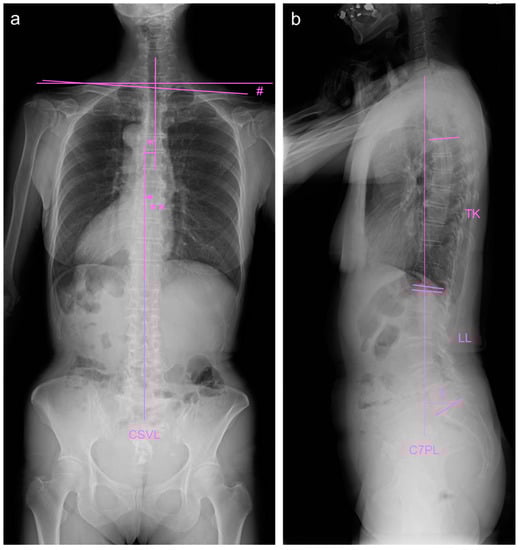

2.4. Image Examinations after Six Months of Daily Physical Exercise